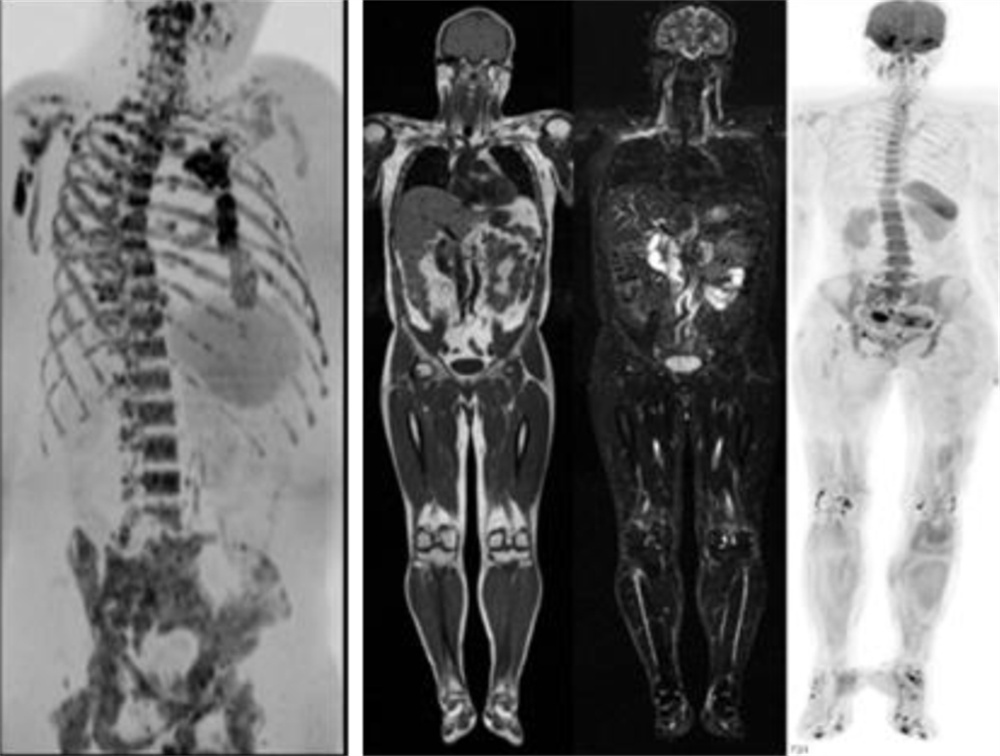

在全身弥散加权成像的同时,可进行磁共振全身扫描,增加肿瘤检出敏感性。

临床应用范围:寻找恶性肿瘤原发灶;恶性肿瘤分期;全身转移灶筛查;淋巴结转移筛查;术后放化疗疗效监测;恶性血液肿瘤疗效观察;体检与肿瘤筛查。

亮血:血管狭窄筛查。黑血:血管壁斑块成像。